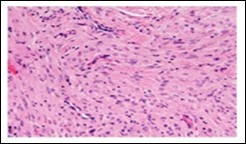

Figure 1.Soft tissue perineurioma with fascicles of bipolar neural cells with elongated cytoplasmic processes, wavy nuclei  and an admixture of collagen fibres 11.

Soft tissue perineurioma with fascicles of bipolar neural cells with elongated cytoplasmic processes, wavy nuclei  and an admixture of                 collagen fibres 11.